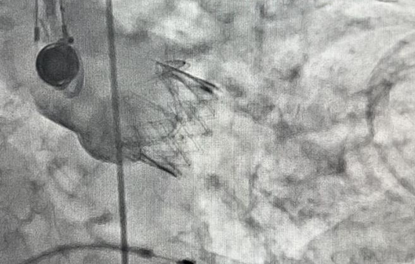

手术过程中,李学文主任在患者左侧胸壁切开一3~4厘米的小切口,在X线和经食道心脏超声的引导下,协同助手张国安、王沙将折叠在导管里的人工生物瓣膜经患者心尖输送至主动脉瓣所在位置,然后释放出人工瓣膜并退出导管,手术的主要步骤即告完成。术后两小时,患者顺利苏醒,次日转出心外ICU进入普通病房,术后第五日康复出院。

经心尖置入的主动脉瓣人工瓣膜